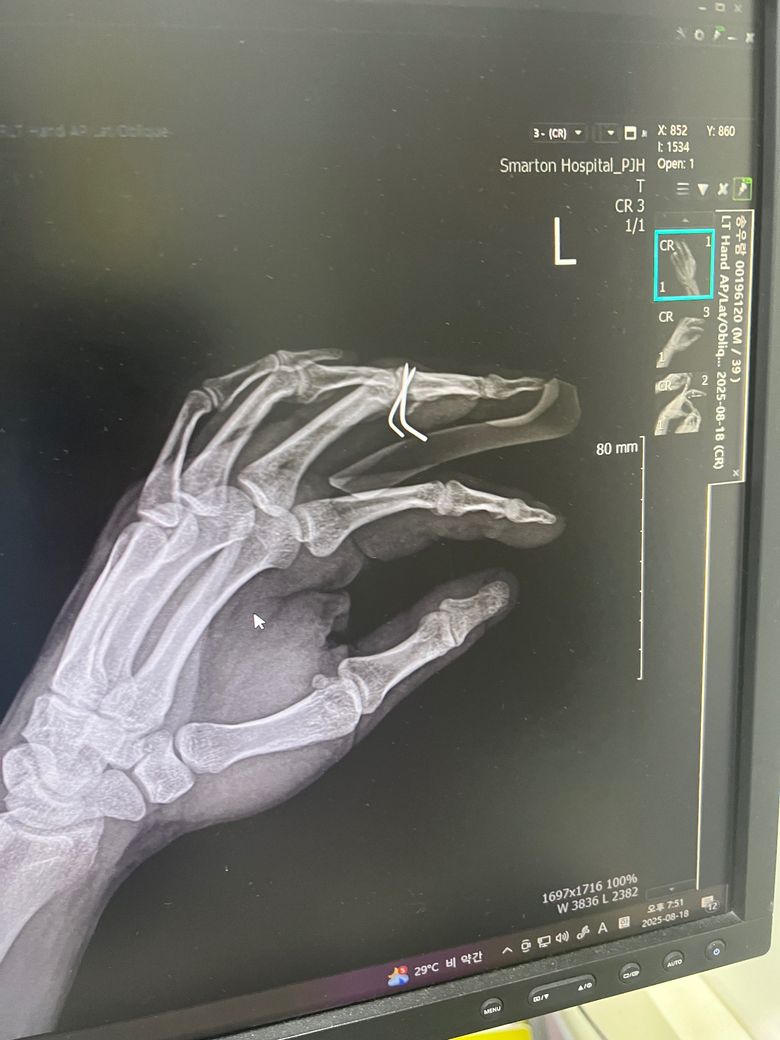

중지 손가락 골절 후 핀 박았습니다 그런데

4주정도 있어야 한다는데 2주만에 뽑은 환자도 있다는데 그게 가능할까요? 사람마다 차이가 있지만 그게 실현 가능한 일인지 궁금합니다.

• 1번 째 사진